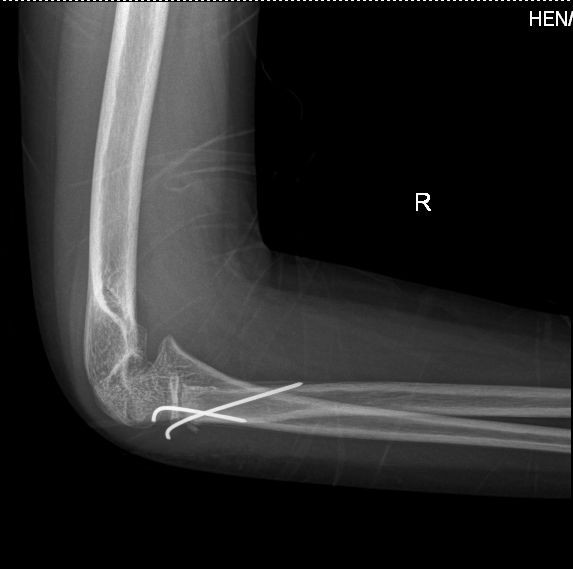

儿童右尺骨鹰嘴骨折

照x光片发现尺骨近端骨折.